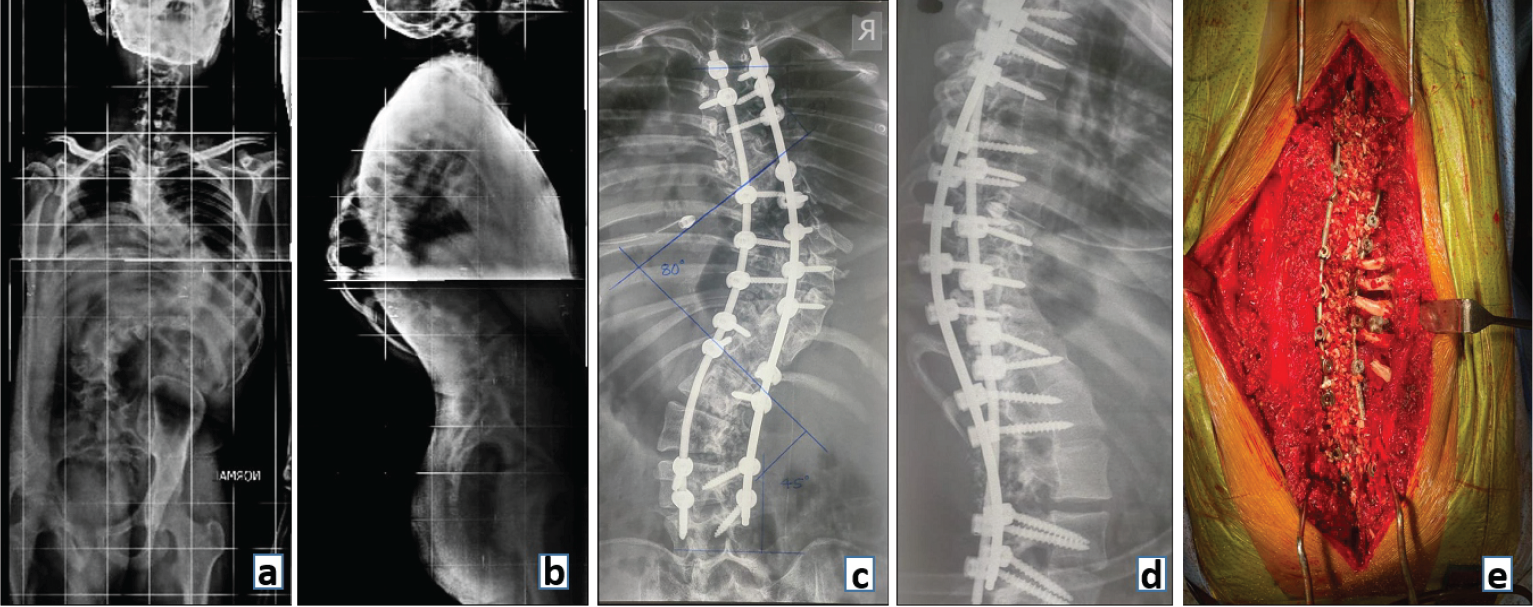

In the spine surgery of today, instrumented fusion involves fusion supported by pedicle screws and rods. The instrumentation provides short-term stability (months) to the spine until long-term stability is achieved by bony fusion of the spinal segments. It is an ongoing race between implant failure and bony fusion as to which comes first! (Fig. 9).

Figure 9: Preoperative radiograph (a) anteroposterior and (b) lateral view showing a Double Major Curve Lenke type 3 adolescent idiopathic scoliosis. Postoperative (c) Anteroposterior and (d) Lateral radiograph showing deformity correction with fusion and posterior stabilization with (e) clinical image demonstrating bone graft laid across the fusion bed prepared by decorticating laminae and removing spinous processes.